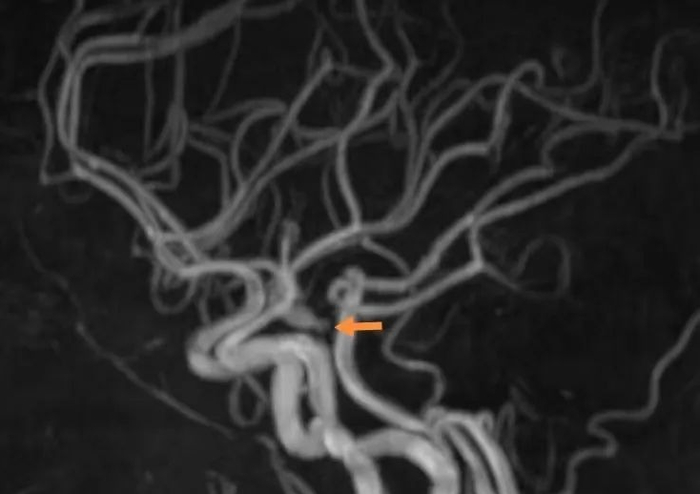

▲术前检查,箭头所指为动脉瘤

▲DSA示动脉瘤栓塞前后对比